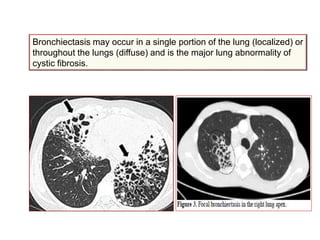

Bronchiectasis may occur in a single portion of the lung (localized) or

throughout the lungs (diffuse) and is the major lung abnormality of

cystic fibrosis.